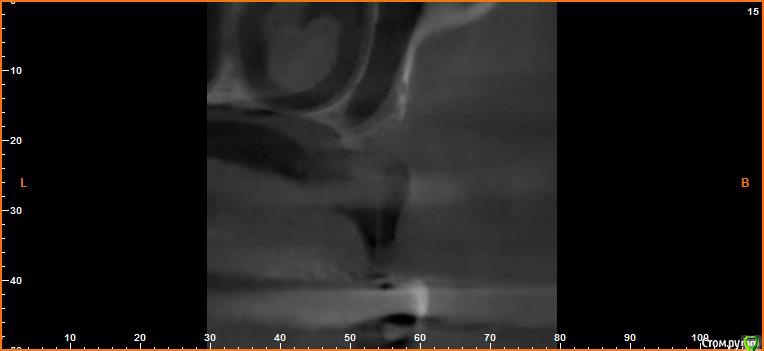

борисович Опубликовано 16 февраля, 2017 Автор Поделиться Опубликовано 16 февраля, 2017 Если сделать только синус получиться поставить импланты только в проекции 16,17 . В проекции 14,15 строение гайморовой пазухи узкое очень, вы думаете не стоит заниматься вертикалью? Спасибо за ответ Ссылка на комментарий